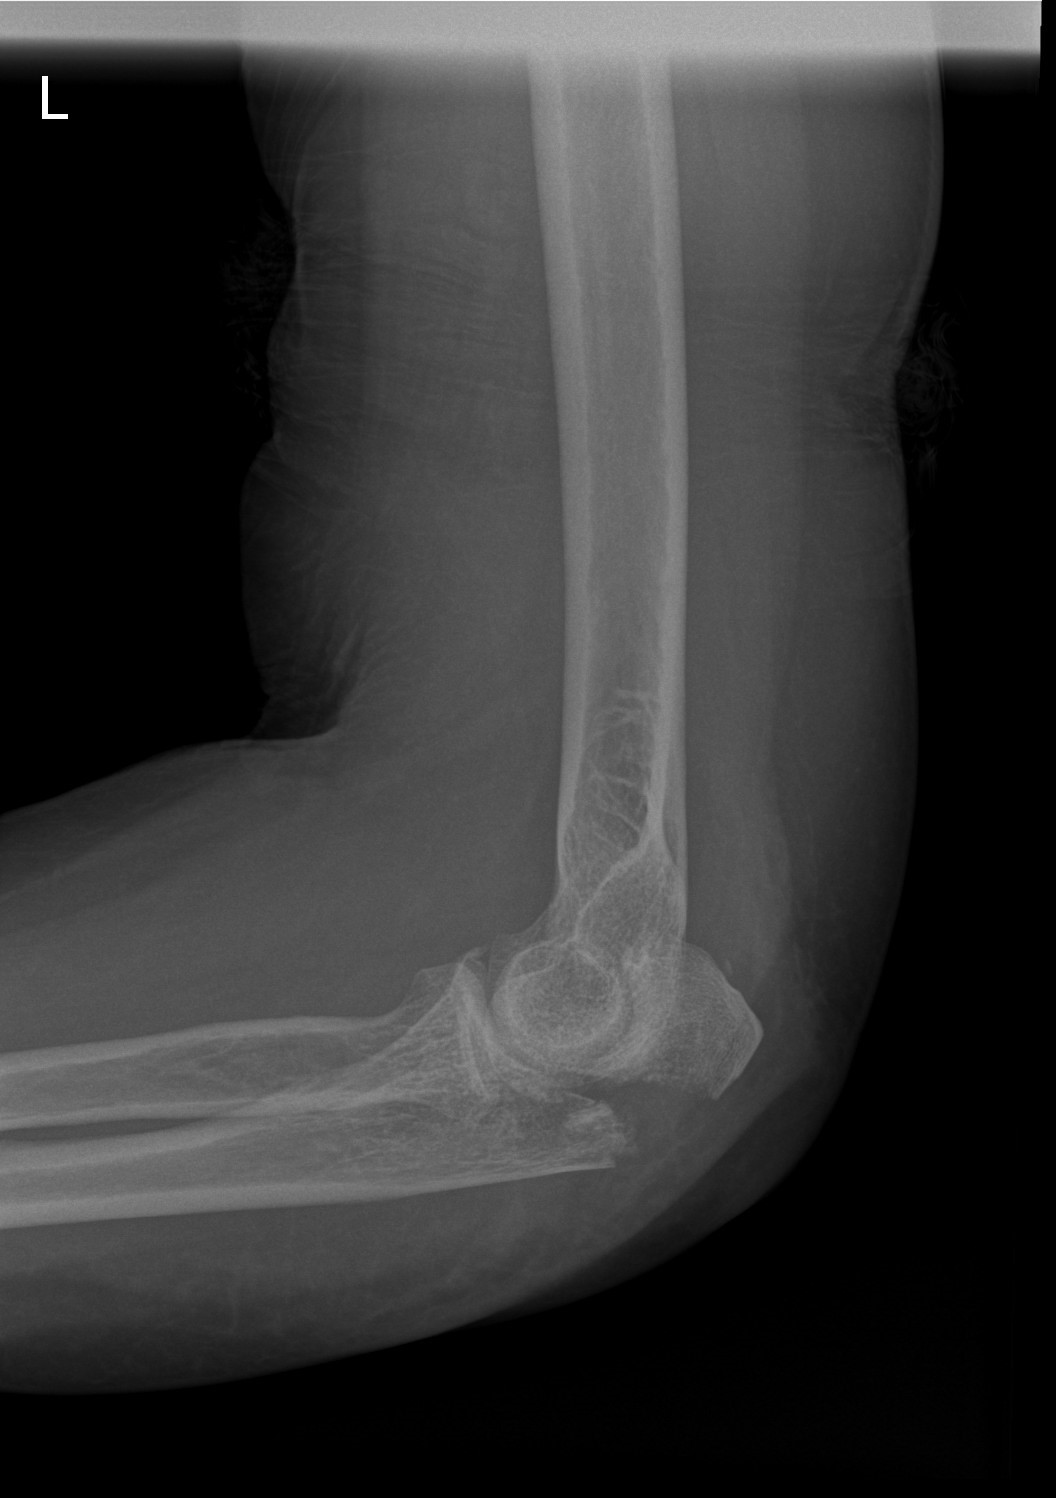

Olecranonfractuur

Breuk van de elleboogpunt na val of trauma? Olecranonfractuur diagnose en operatieve behandeling door ellebooogspecialisten in Orthopedie Turnhout.